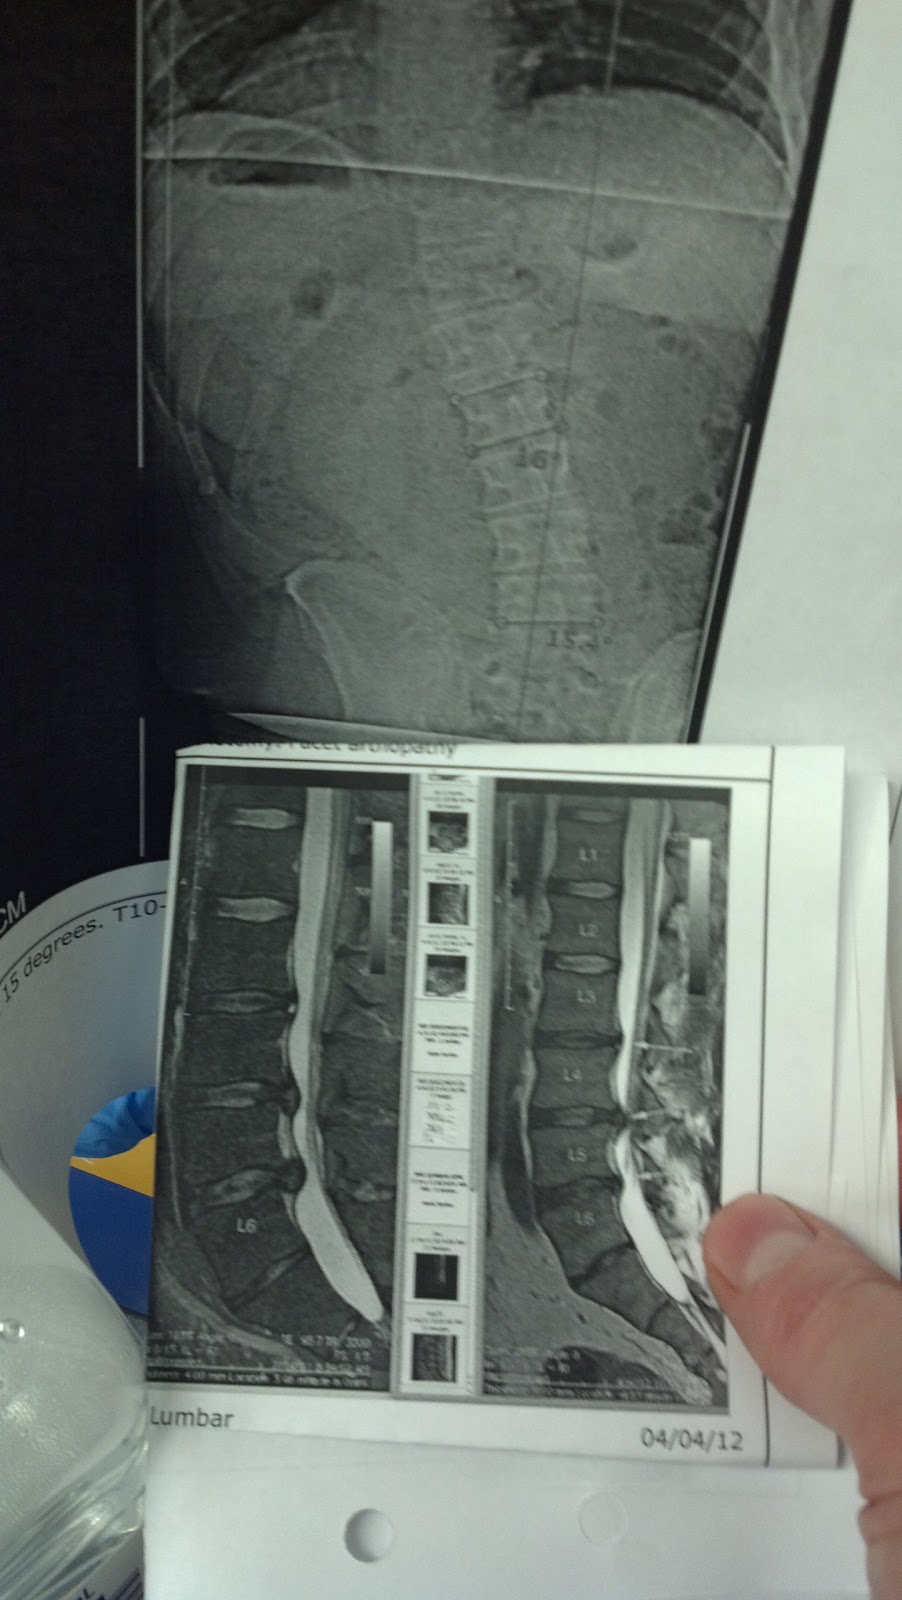

38 yo executive with huge trunk shift scoliosis caused by huge disc Trunk Shift Scoliosis trunk imbalance (ie, frontal trunk shift measured with a plumb line from c7 to s1) is part of the clinical evaluation. the goal of the side shift method of scoliosis treatment is the active correction of the spinal curve directed at. The left end of the. trunk shift is defined as a distance greater than 2 cm. Trunk Shift Scoliosis.

38 yo executive with huge trunk shift scoliosis caused by huge disc Trunk Shift Scoliosis trunk shift is defined as a distance greater than 2 cm between the vtrl and the center sacral vertical line. you stand in a relaxed position with your arms at your sides and the doctor will view you from behind looking for curvature of the spine, shoulder blade. the goal of the side shift method of scoliosis. Trunk Shift Scoliosis.

Sciatica Scoliosis, Lumbar Disc Herniation L4L5S1, Lateral Shift Trunk Shift Scoliosis trunk imbalance (ie, frontal trunk shift measured with a plumb line from c7 to s1) is part of the clinical evaluation. trunk shift is defined as a distance greater than 2 cm between the vtrl and the center sacral vertical line. The left end of the. Posteroanterior radiography was used to show the apex of the thoracic curve.. Trunk Shift Scoliosis.